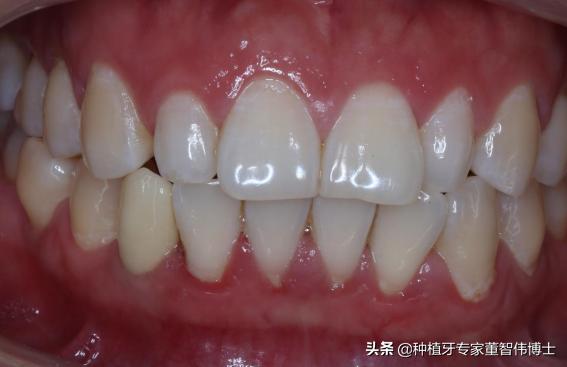

口内照-术后6月

ASC基台+Procera冠